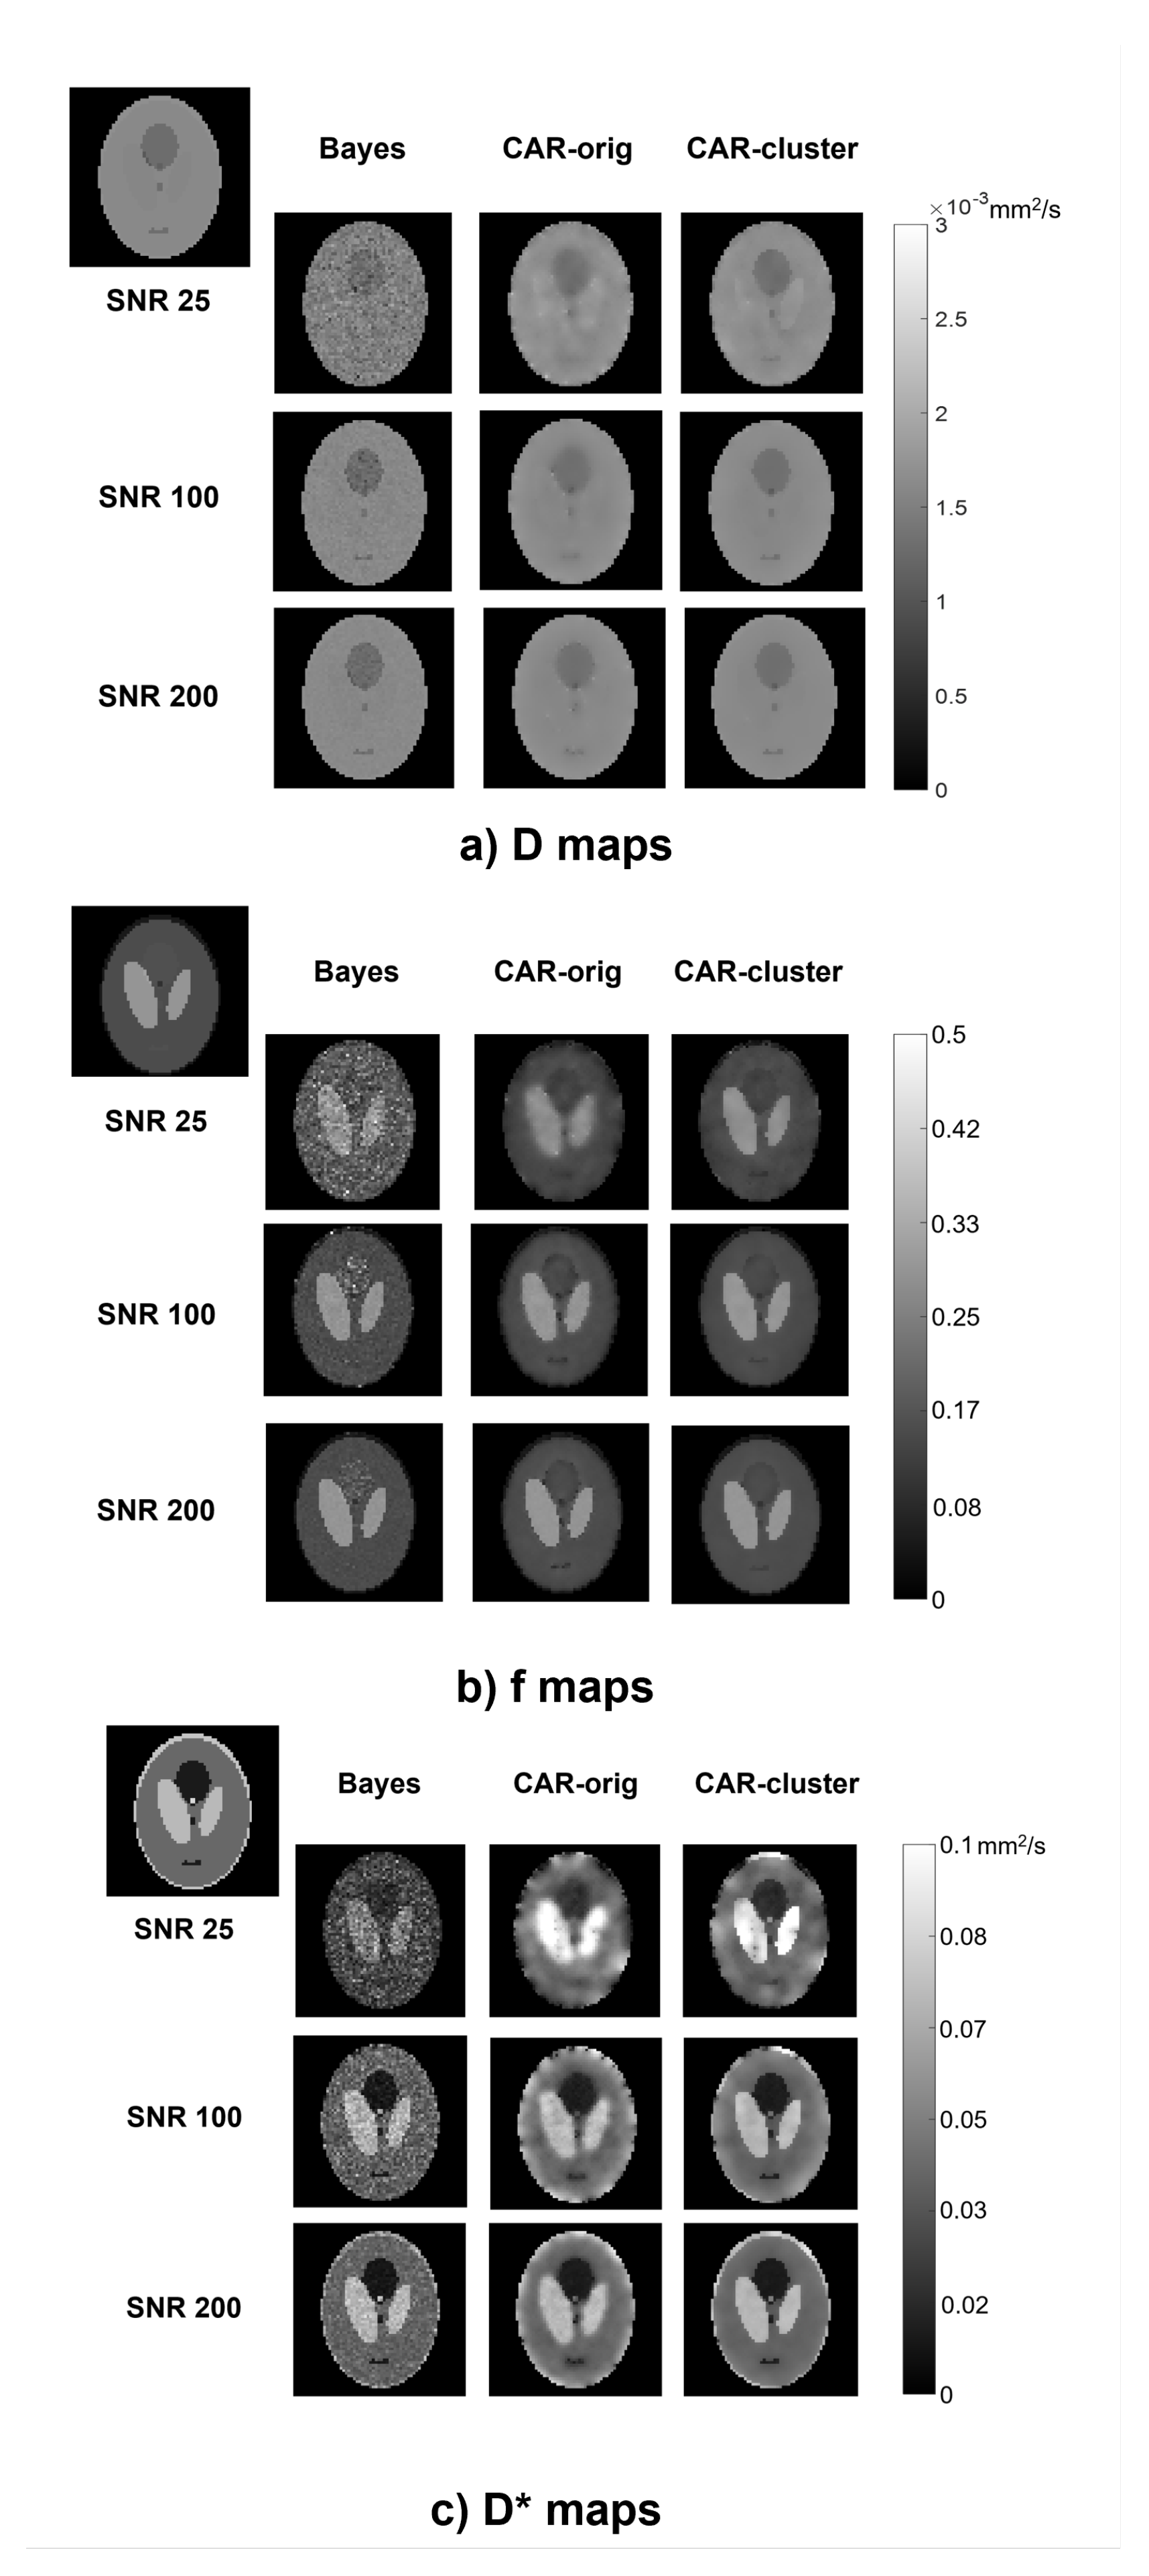

The qualitative comparison of the estimated maps among the three different methods revealed that the CAR clustering approach was able to improve their quality with respect to the Bayesian CAR method without clustering and the state-of-the-art Bayesian approach without CAR (Figure 2).

Figure 2.

Parametric maps of D (a), f (b) and (c), estimated from a simulated image using the three methods (columns) at different values (rows). The true maps are also reported in the top left corner.

The Bayesian estimation without CAR generated maps with high contrast between different structures, but maintained a certain level of noise throughout the image, especially at low values. On the contrary, the CAR approach without clustering was able to generate homogeneous values within the ROIs, but at the same time it lost the boundaries between the regions and introduced blurring and blotchy artifacts, especially at low values and for . Instead, the proposed approach with clustering better highlighted the contrast between structures at the interfaces, and preserved a high homogeneity within the regions; therefore, it retained the advantages of both other methods.